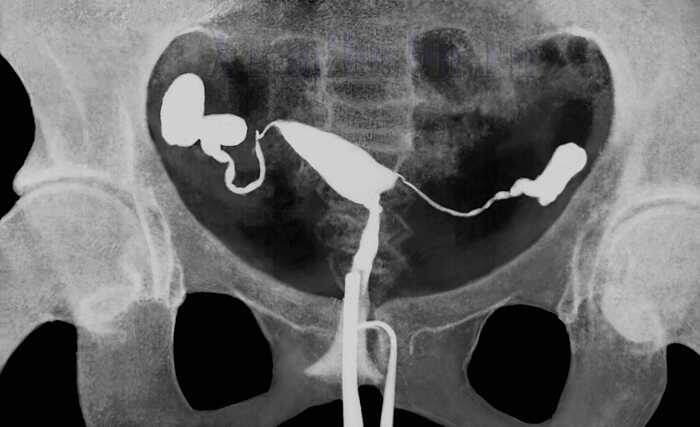

ГСГ (гистеросальпингография) показала проходимость обеих маточных труб. Однако, согласно данным литературы, в 20-42% случаев при нормальной ГСГ лапароскопия выявляет спаечный процесс, который не был диагностирован. У нашей пациентки сохранялось подозрение на трубно-перитонеальный фактор.

Проведена диагностическая лапароскопия, во время которой выявлены перитубарные спайки (спайки вокруг маточной трубы, они затрудняли проход яйцеклетки из яйника в трубу). Спайки были рассечены, восстановлена анатомическая подвижность труб и их взаимоотношение с яичниками.